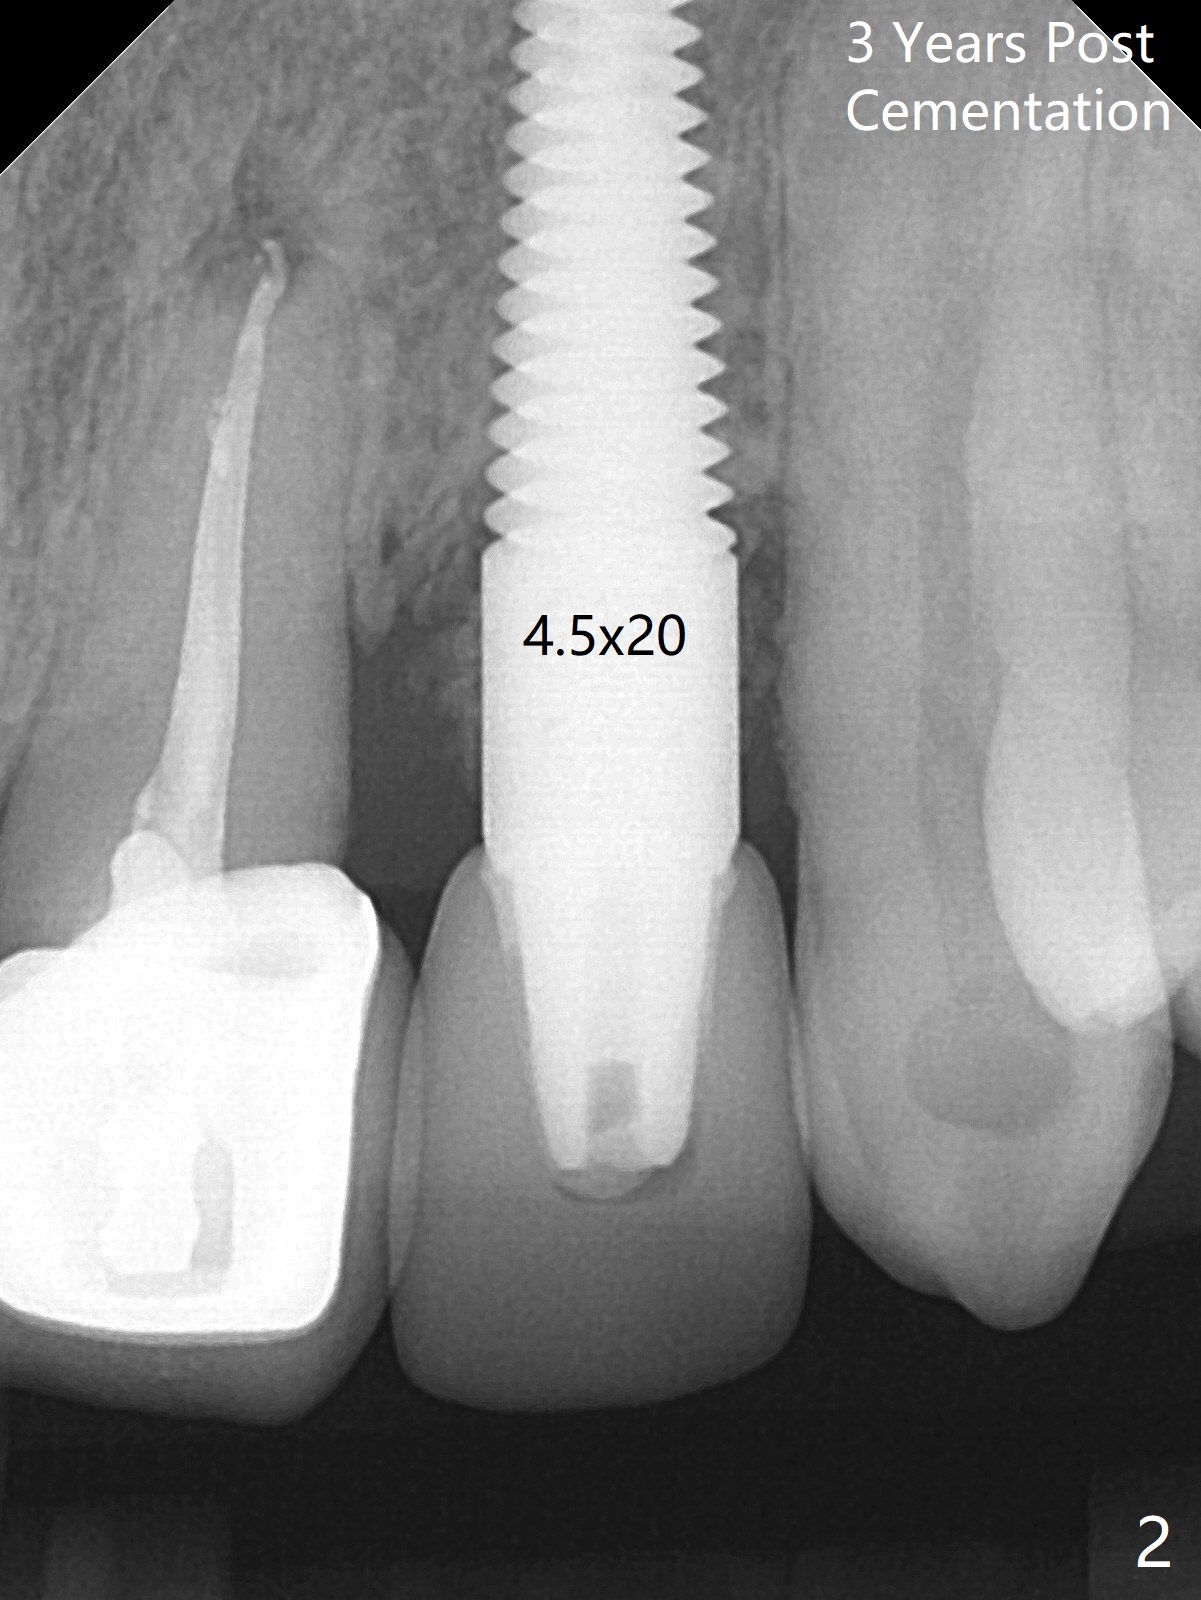

59岁女,口腔卫生差,害怕治疗,左上侧切牙即种牙冠粘固后6年4个月,同意深洗(图三)。虽然软硬组织没有特殊变化,再细点植体可能更好些(图一,二)。